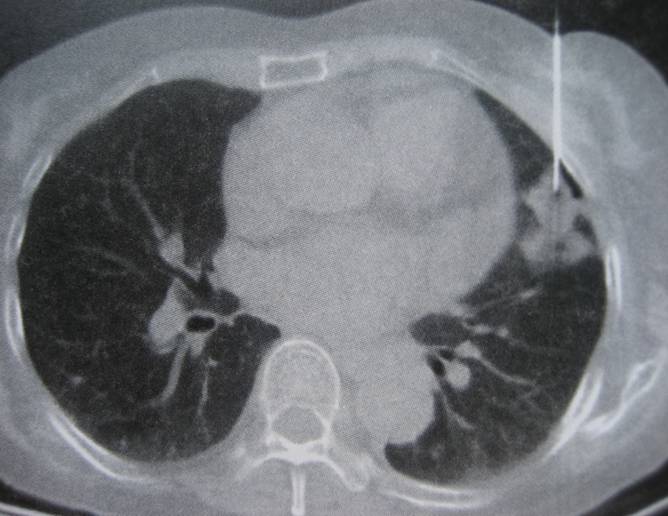

图片:CT引导下经皮肺穿刺活检